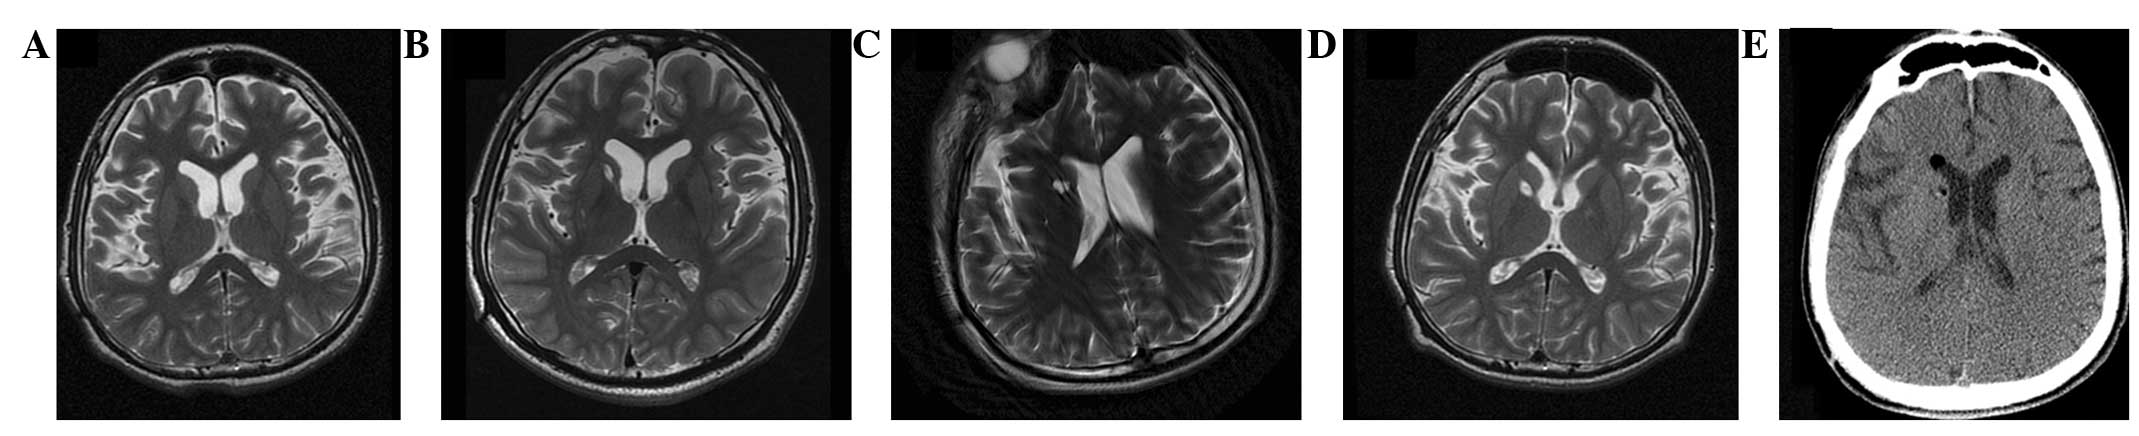

(A) 術(shù)前 MRI 顯示腦萎縮。 (BD)術(shù)后1年、3年、4年MRI與術(shù)前MRI相比無明顯變化。 (E) 術(shù)后3天,計(jì)算機(jī)斷層掃描顯示沒有出血或水腫。

遺傳分析、影像觀察和隨訪

遺傳分析發(fā)現(xiàn)患者DYT1 ( TOR1A )第五外顯子存在突變 (907-909 delGAG) 。他對神經(jīng)外科手術(shù)表現(xiàn)出良好的耐受性,并于4點(diǎn)出院。沒有與細(xì)胞植入或外科手術(shù)相關(guān)的嚴(yán)重不良事件。POD時(shí)的CT掃描顯示沒有出血或水腫(圖2e)。術(shù)后1個(gè)月,患者的PTD癥狀開始改善。BFMDMS逐漸增加,從術(shù)前的21分別增加到術(shù)后1、2、3和4年的18、17、15和13,術(shù)后4年改善38.1%(表1)。

CT(圖1b-e)和MRI(圖2b-d)掃描顯示4年隨訪期間沒有顯著變化。 手術(shù)前1天(圖1f)和手術(shù)后1、2、3和4年(圖1g-j) 獲得18F-FDGPET掃描。術(shù)后雙側(cè)植入部位豆?fàn)詈撕颓鹉X18F-FDG攝取值較術(shù)前增加。這一結(jié)果表明,自移植以來,葡萄糖代謝逐年略有增加。